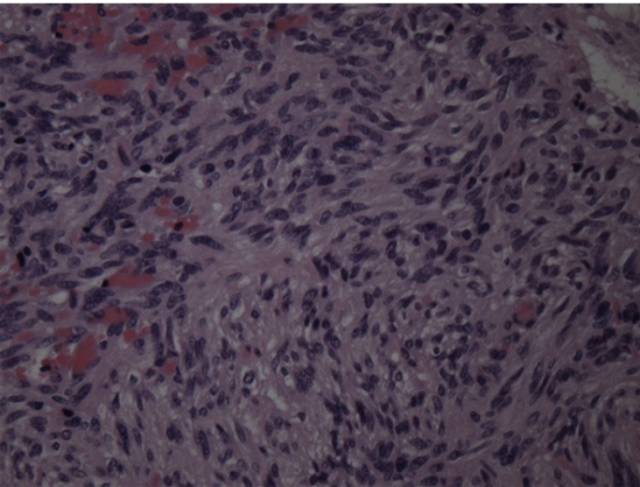

HE染色示:过度型脑膜瘤(同时含有上皮型脑膜瘤和纤维性脑膜瘤的病理特点),可见椭圆形及细长形肿瘤细胞,细胞边界不清,胶质纤维较少。